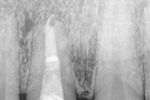

Die orthograde Revision bei persistierender Parodontitis apicalis nach Wurzelspitzenresektionen.

Autor(en): Hülsmann M, Drebenstedt S, Nordmeyer S et al.

Fundstelle: Endodontie 2011; 20: 251–267

Die Erfolgsquote von Wurzelspitzenresektionen wird in der Literatur mit 25 % bis 99 % angegeben1. Bei Scheitern eines apikalchirurgischen Eingriffs galt der Zahn bislang häufig als austherapiert und die Extraktion als die Therapie der Wahl. Alternativ wurde eine erneute Resektion vorgeschlagen. In einer Reihe von Falldarstellungen wird von Versuchen berichtet, mithilfe modernen Instrumentariums (Ultraschall und Dentalmikroskop) und neuer Materialien (MTA) diese Fälle nicht-chirurgisch durch eine rein orthograde Revision zu behandeln. Der folgende Beitrag soll das derzeitige Wissen hierzu zusammenfassen, die Vorschläge zur Vorgehensweise bei orthograder Revision nicht erfolgreicher Wurzelspitzenresektionen vorstellen und Möglichkeiten sowie Grenzen dieser Therapieoption aufzeigen.